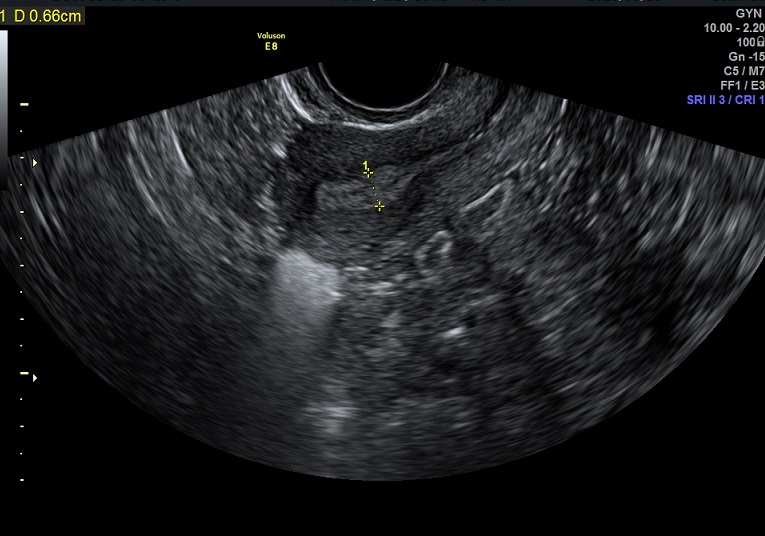

2015-3-10 月经第19天检查

内膜厚0.7cm

内膜血流:2级

内膜波动可见